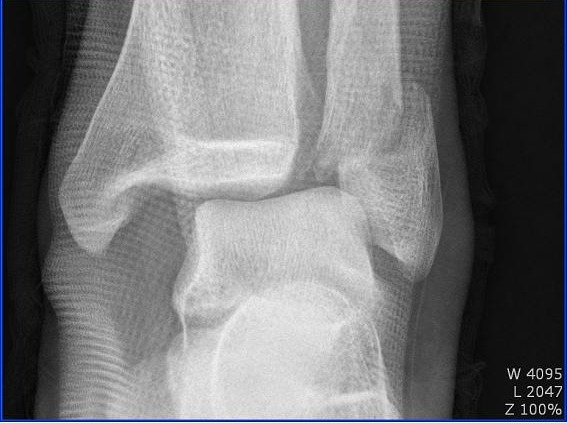

<11월 9일> 수술

- 외과 골절 및 내외측 인대파열이라는 진단을 받았는데 골절부분만 수술